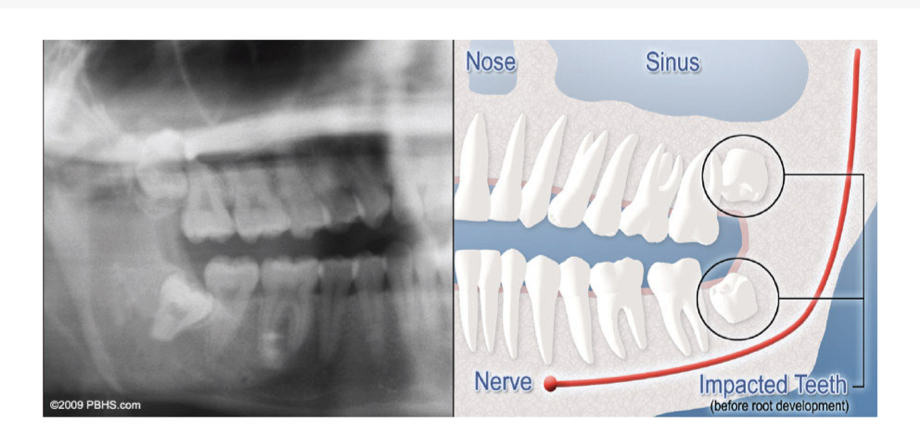

Cuando un diente no crece completamente, se ve impactado; por lo general, no puede atravesar las encías porque no hay suficiente espacio.

Aunque la mayoría de las personas desarrollan y crecen 32 dientes permanentes permanentes, muchas veces sus mandíbulas son demasiado pequeñas para acomodar las cuatro muelas del juicio. Cuando el espacio inadecuado impide la erupción de los dientes, se denominan impactados. Esto indica su incapacidad para ponerse en la posición adecuada para masticar y limpiar.

Tipos de Impactaciones

Tendremos que verlo para una consulta para determinar si se beneficiará de la extracción de la muela del juicio. Se tomará una radiografía especial de su boca y mandíbula (panorex) para determinar si sus muelas del juicio están impactadas, si hay espacio para que erupcionen y qué tan difícil será extraerlas.

- Impactación de tejidos blandos: no hay suficiente espacio para permitir que el tejido de las encías se retraiga para una limpieza adecuada del diente.

- Impactación ósea parcial: hay suficiente espacio para permitir que la muela del juicio erupcione parcialmente. Sin embargo, el diente no puede funcionar correctamente en el proceso de masticación y genera problemas de limpieza, entre otros.

- Impactación ósea completa: NO hay espacio para que salga el diente. Permanece incrustado en la mandíbula o, si es parcialmente visible, requiere técnicas quirúrgicas complejas para su extracción. La muela del juicio impactada también puede estar en una posición inusual y difícil de extraer. Esta situación también puede surgir cuando la forma o el tamaño de la mandíbula y otras estructuras faciales hacen que la extracción de este diente sea significativamente más compleja.